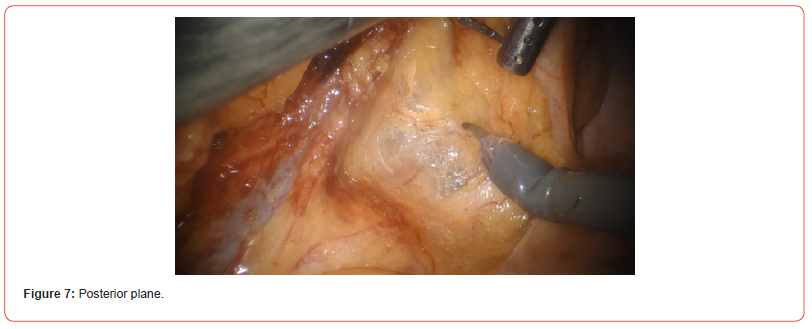

7. Posterior plane

As you can see in this picture the anterior approach first you can provide a good exposition of the anterior organs, and you can have more traction before starting the posterior dissection.